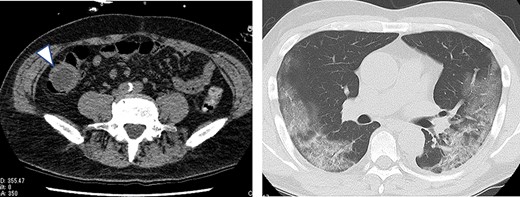

A 63-year-old male who had fever and dyspnea visited a medical institution. Both antigen and polymerase chain reaction (PCR) tests for SARS-CoV-2 were positive and he was hospitalized for treatment. Nine days after admission, he was transferred to our hospital due to deteriorating respiratory condition. After admission to our hospital, ventilator management and steroid administration were performed. After 3 days, his respiratory condition improved and he was able to withdraw from the ventilator. Computed tomography (CT) taken for observation of lung disease coincidentally showed cystic lesions in the right abdomen (Fig. 1). He had no abdominal symptoms at this time. The patient was discharged on the 18th day of hospitalization. He had diarrhea from the 15th day after discharge and abdominal pain from the next day. He consulted his family doctor on the 17th day because the abdominal pain persisted. CT examination revealed enlargement of cystic lesion and intussusception of the right colon (Fig. 2). The patient was transferred to our hospital as an emergency case. Physical findings showed fever with a body temperature of 38°C and tenderness in the right lower abdomen. Blood test showed an inflammatory reaction with a white blood cell count of 13 000/μl and C-reactive protein of 2 mg/dl. The SARS-CoV-2 PCR testing was negative. We performed emergency surgery on the same day.

Plain CT on the 13th day after COVID-19 onset (the day after withdrawal from the ventilator); a cystic lesion was found in the right lower abdomen (arrowhead).

Plain CT taken when the patient was transferred to our hospital for abdominal pain; the cystic lesion had increased in size (arrowhead) and showed intussusception.